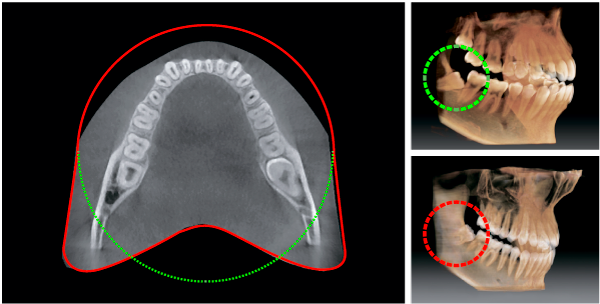

Инновационная форма объема PaX-i3D обеспечивает сканирование в форме зубной дуги и показывает весь зубной ряд, в отличии от других аппаратов с аналогичным по размеру FOV (зоны сканирования). Обычно 10X8.5см достаточно для сканирования зубов мудрости. Тем не менее, когда они лежат на боку, существует высокая вероятность того, что они не попадут в зону сканирования. FOV в форме зубной дуги устраняет эту вероятность, показывая скрытую область.